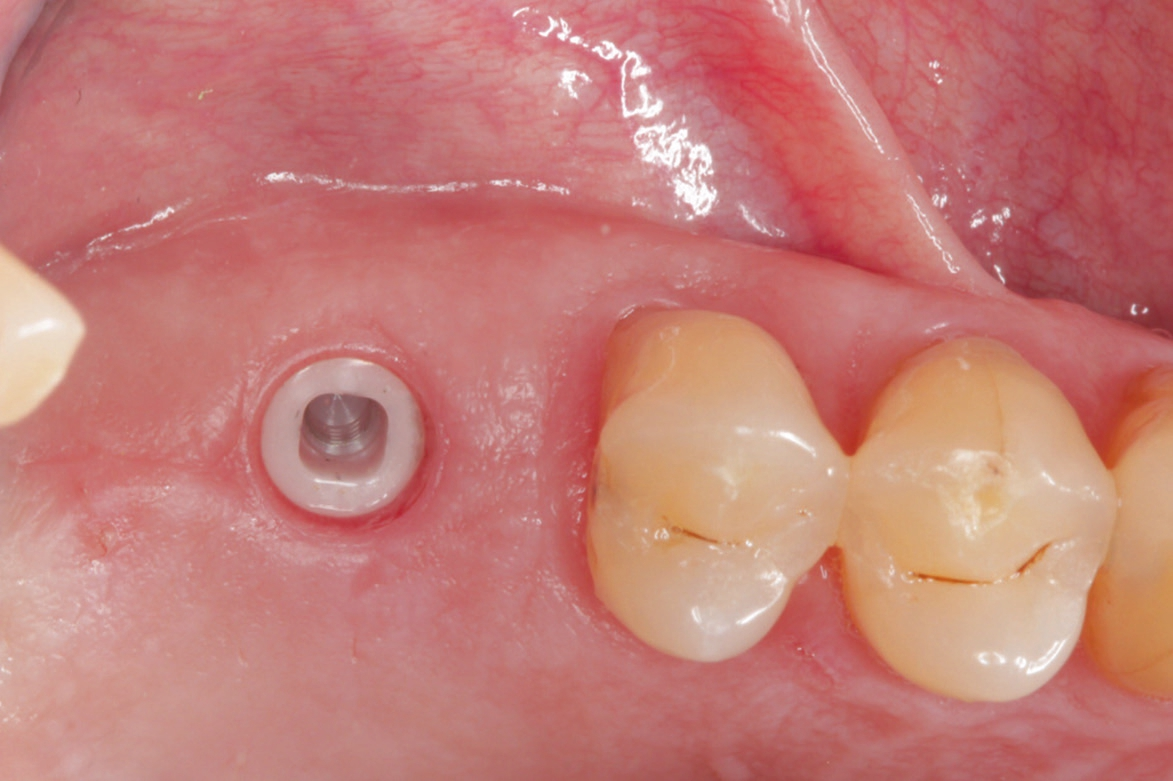

Nach lokaler Anästhesie wurden ein Kieferkammschnitt und eine nur minimale Mobilisation des Mucoperiostlappens durchgeführt. Beim internen Sinuslift nach Summers wird die Pilotbohrung bis ca. 1 mm vor die Begrenzung der Kieferhöhle vorgenommen und je nach Knochenangebot und Qualität mittels verschiedener Osteotome (Institut Straumann) weiter aufbereitet. Unabdingbar ist dabei die regelmäßige Kontrolle der Unversehrtheit der Schneider‘schen Membran durch einen „Nasenblasversuch“. Nach erfolgreicher Aufbereitung des Lagers konnte ein Implantat Größe 4,1/10 mm sehr gut primärstabil inseriert werden, anschließend primärer Wundverschluss mittels 5/0 monophiler Naht. Nach vier Monaten erfolgte die minimalinvasive Freilegung und Applikation des Gingivaformers.